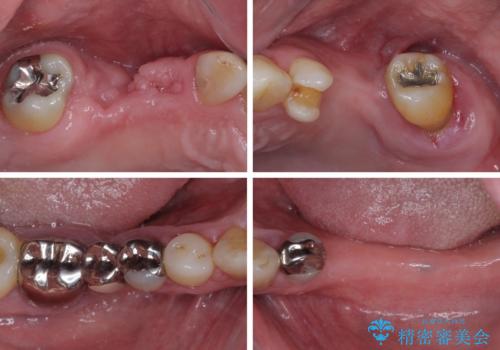

欠損の多い奥歯 インプラントによる補綴治療

- 50代男性

- 地元ではなかなかインプラント治療を行ってくださる医院がないとのことで、転勤で東京にいる期間に治療を行いたいとのことで来院された患者様です。

上顎は左右ともに骨が少ない状態であり、特殊なドリルを用いた歯槽骨の拡大や自家骨挙上などを行いながらインプラントを埋入していくこととしました。

右下の銀歯も気になるとのことで、インプラント治療と並行してオールセラミックによるブリッジ補綴治療も行うこととしました。